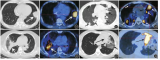

• 飞利浦Rembra平台三款CT成像系统获FDA认证

皇家飞利浦公司旗下Rembra平台的一系列CT成像系统近日获得FDA 510(k)认证。总部位于阿姆斯特丹的飞利浦公司称,此次获批的系统有Rembra CT、Rembra RT和Areta RT三款。这些产品主要针对急诊和肿瘤科领域不断增长的成像量与复杂性问题。其中,Rembra CT专为急诊科和重症监护室等高通量环境打造。该系统采用85厘米孔径,可支持大范围成像,日处理能力高达270例检查。它能在时间紧迫时,实现快速图像采集和重建,且不降低诊断质量。Rembra平台还延...